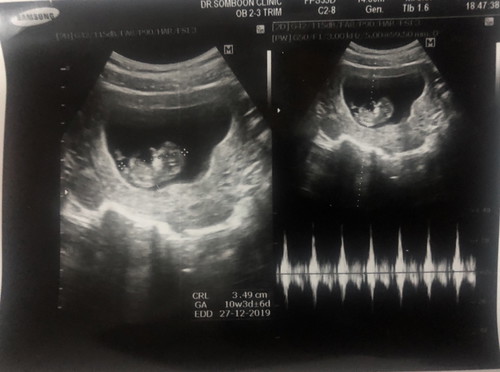

10 Weeks

Đọc thêmรูปตอน10สัปดาห์ค่ะ เราแพ้ท้องตั้งแต่10สัปดาห์แรกเลยค่ะตอนนี้เรา16สัปดาห์ก็ยังแพ้อยุ่แพ้หนักสุดเหม็นมากคือ หมู หมูสามชั้น เบค่อน ของมันๆเลี่ยนๆไม่ได้เลยค่ะ น้ำหนักลดลงมากค่ะ ตอนนี้หนักแค่46โลเองค่ะ แต่กินผักผลไม้เยอะๆค่ะ กินนมบำรุงค่ะ